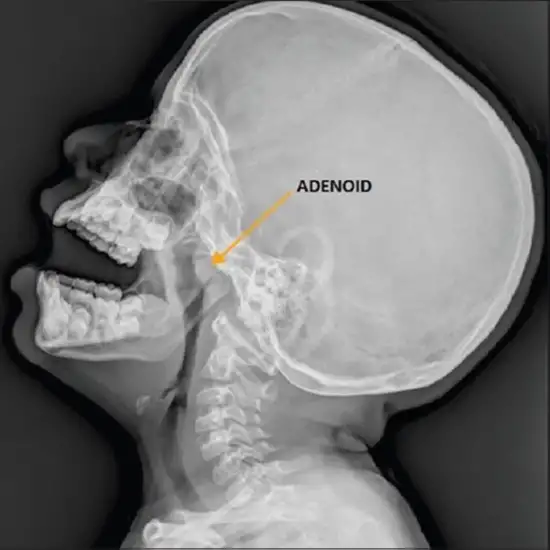

X-rays are utilized to confirm the diagnosis of soft tissue problems in the affected body part. The neck is irradiated by an X-ray machine, which captures an image on a computer. This picture depicts the cervical vertebrae, enlarged adenoids and tonsils, oral and nasal airways, and the nasopharynx (where the two airways meet).

X-ray Naso-pharynx, LAT View testis conducted to identify long face syndrome (adenoid face in infants) and diagnose nasal cancer, tumor, or cyst. It gives a dependable method for determining if a problem is clinically essential at an early stage.